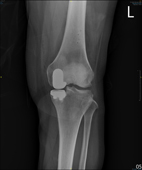

左圖:術前膝關節X光片;右圖:術後膝關節X光片。